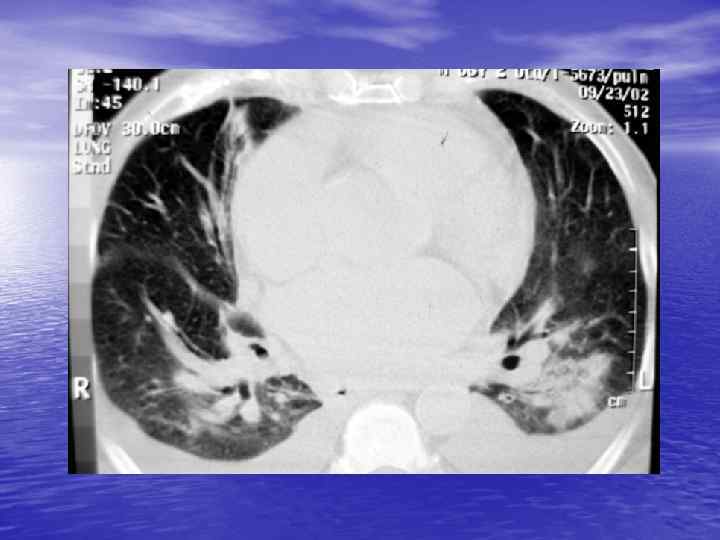

Электронные окна üОкном (Window) называют определенную часть шкалы Хаунсфилда, которой соответствует перепад величины яркости экрана от белого до черного. üШирина окна (Window Width, WW) — это величина разности наибольшего и наименьшего коэффициента ослабления, отображаемых данным перепадом яркости от белого до черного цвета. üУровень окна (Window Level, WL) — это величина коэффициента ослабления, соответствующая середине окна. Изменение уровня окна позволяет перемещать его в сторону больших или меньших значений чисел Хаунсфилда.

Характеристика основных электронных окон Электронное окно WINDOW Уровень окна Ширина окна Мягкотканное Soft +40 500 Легочное Lung -800 1000 Плевральное Pleural -650 -150 1500 -2000 Костное Вone +150+350 1000 -2000

Преимущества спиральной КТ: ü Возможность проведения исследования с болюсным ü ü ü ü ü контрастированием Высокая разрешающая способность; Высокая скорость исследования; Получение высококачественных изображений костных структур; Возможность обследования всего тела; Возможность проведения исследования больных под наркозом; Возможность детальной оценки состояния крупных и периферических сосудов в условиях искусственного контрастирования; Высокая информативность метода при черепномозговых травмах в остром периоде; Ранняя диагностика ишемических и геморрагических инсультов; Метод выбора для диагностики заболеваний легких; Планирование лучевой терапии.